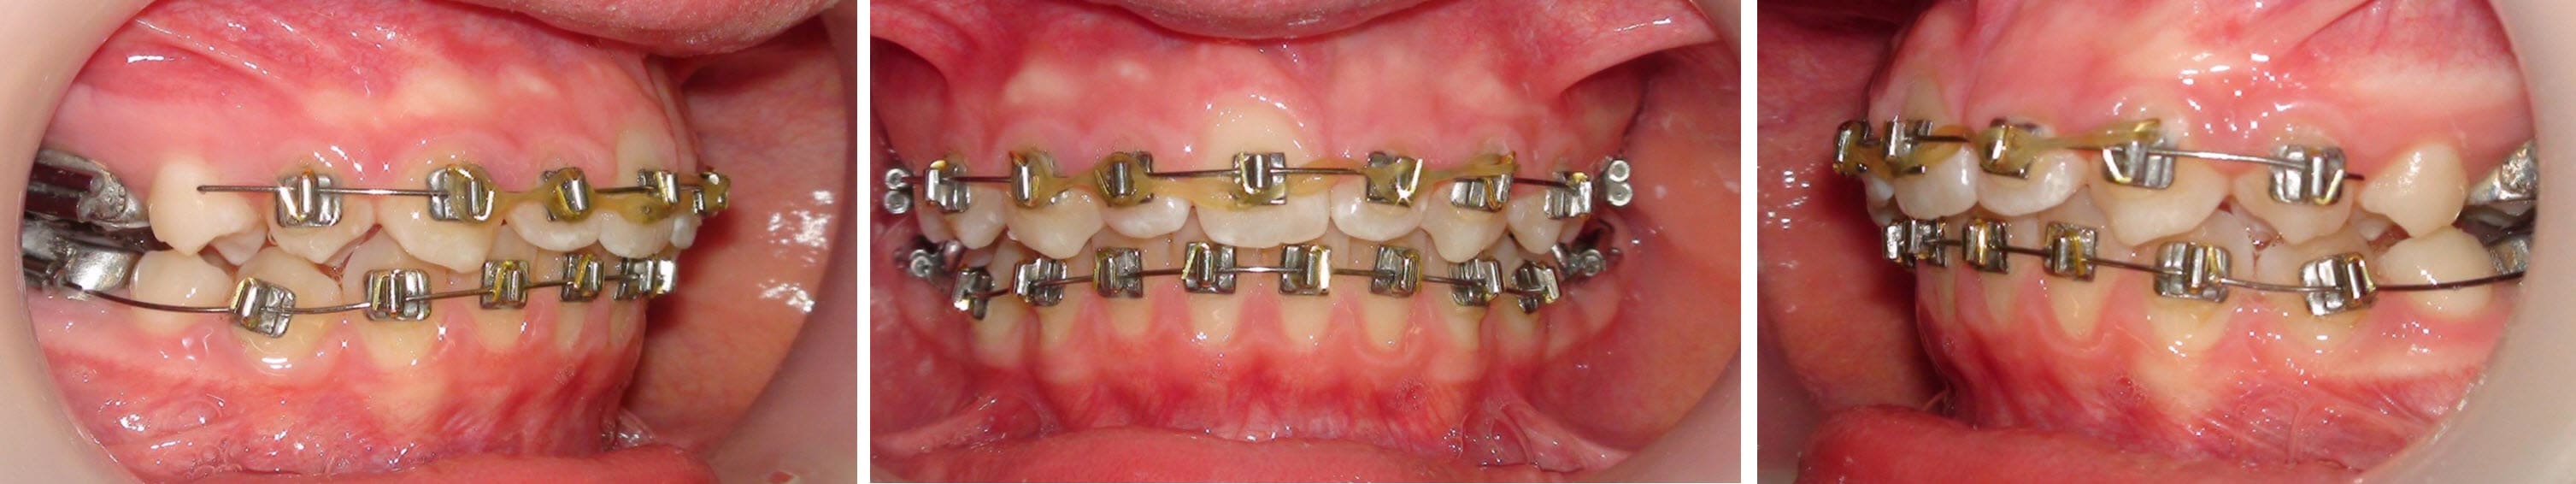

Donc on ferme (images)!

Et après, on fait quoi ?